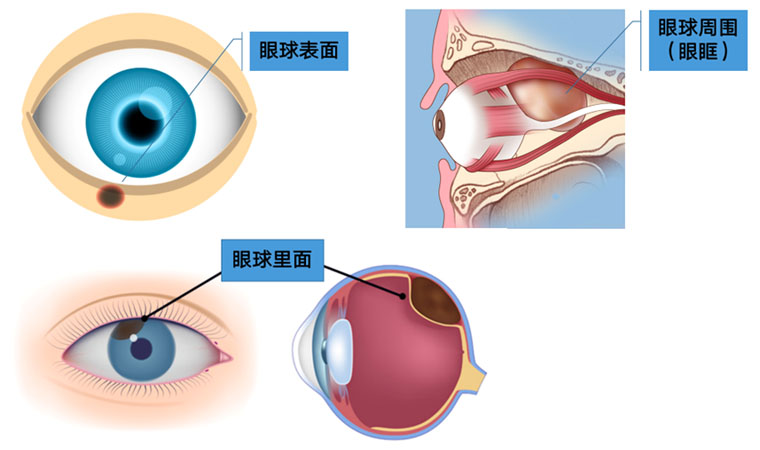

毫無疑問,無論是眼睛表面還是眼睛里面甚至是眼睛周圍,都可能長腫瘤;而且眼部腫瘤也會發生在各個年齡段,包括嬰兒、青少年、中老年都有可能發生眼部腫瘤。但是腫瘤也分良性和惡性,大多數人即使長了腫瘤很有可能是良性的,有一少部分人會得眼部惡性腫瘤。

眼腫瘤包括眼瞼、結膜、眼內、淚器、眼眶腫瘤。眼瞼惡性腫瘤常見基底細胞癌,瞼板腺癌、鱗狀細胞癌和黑色素瘤,良性腫瘤常見于色素痣和血管瘤;眼眶腫瘤包括淋巴瘤、腺樣囊性癌、海綿狀血管瘤、神經鞘瘤、神經纖維瘤等;眼內腫瘤以惡性多見,主要見于視網膜母細胞瘤、脈絡膜黑色素瘤、脈絡膜轉移癌等。

眼睛表面的腫瘤很容易被發現,眼球后邊(也就是眼眶)和眼睛里面的腫瘤常被人忽視或延誤治療,這些隱藏起來的腫瘤會影響眼球的位置,導致眼睛斜視或者眼球慢慢突出。眼睛里面的腫瘤最不容易發現,小孩子有可能表現為瞳孔發白,大人則往往到影響視力了才被發現。